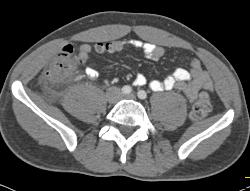

Diagnosis

3D of Small Bowel